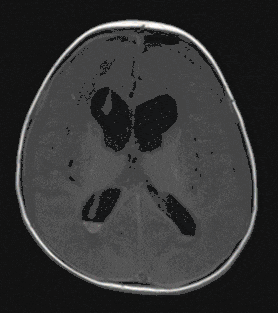

Medulloblastoma

Medulloblastoma is the most common malignant brain tumor in childhood and usually leads to intracranial pressure symptoms due to its growth in size.